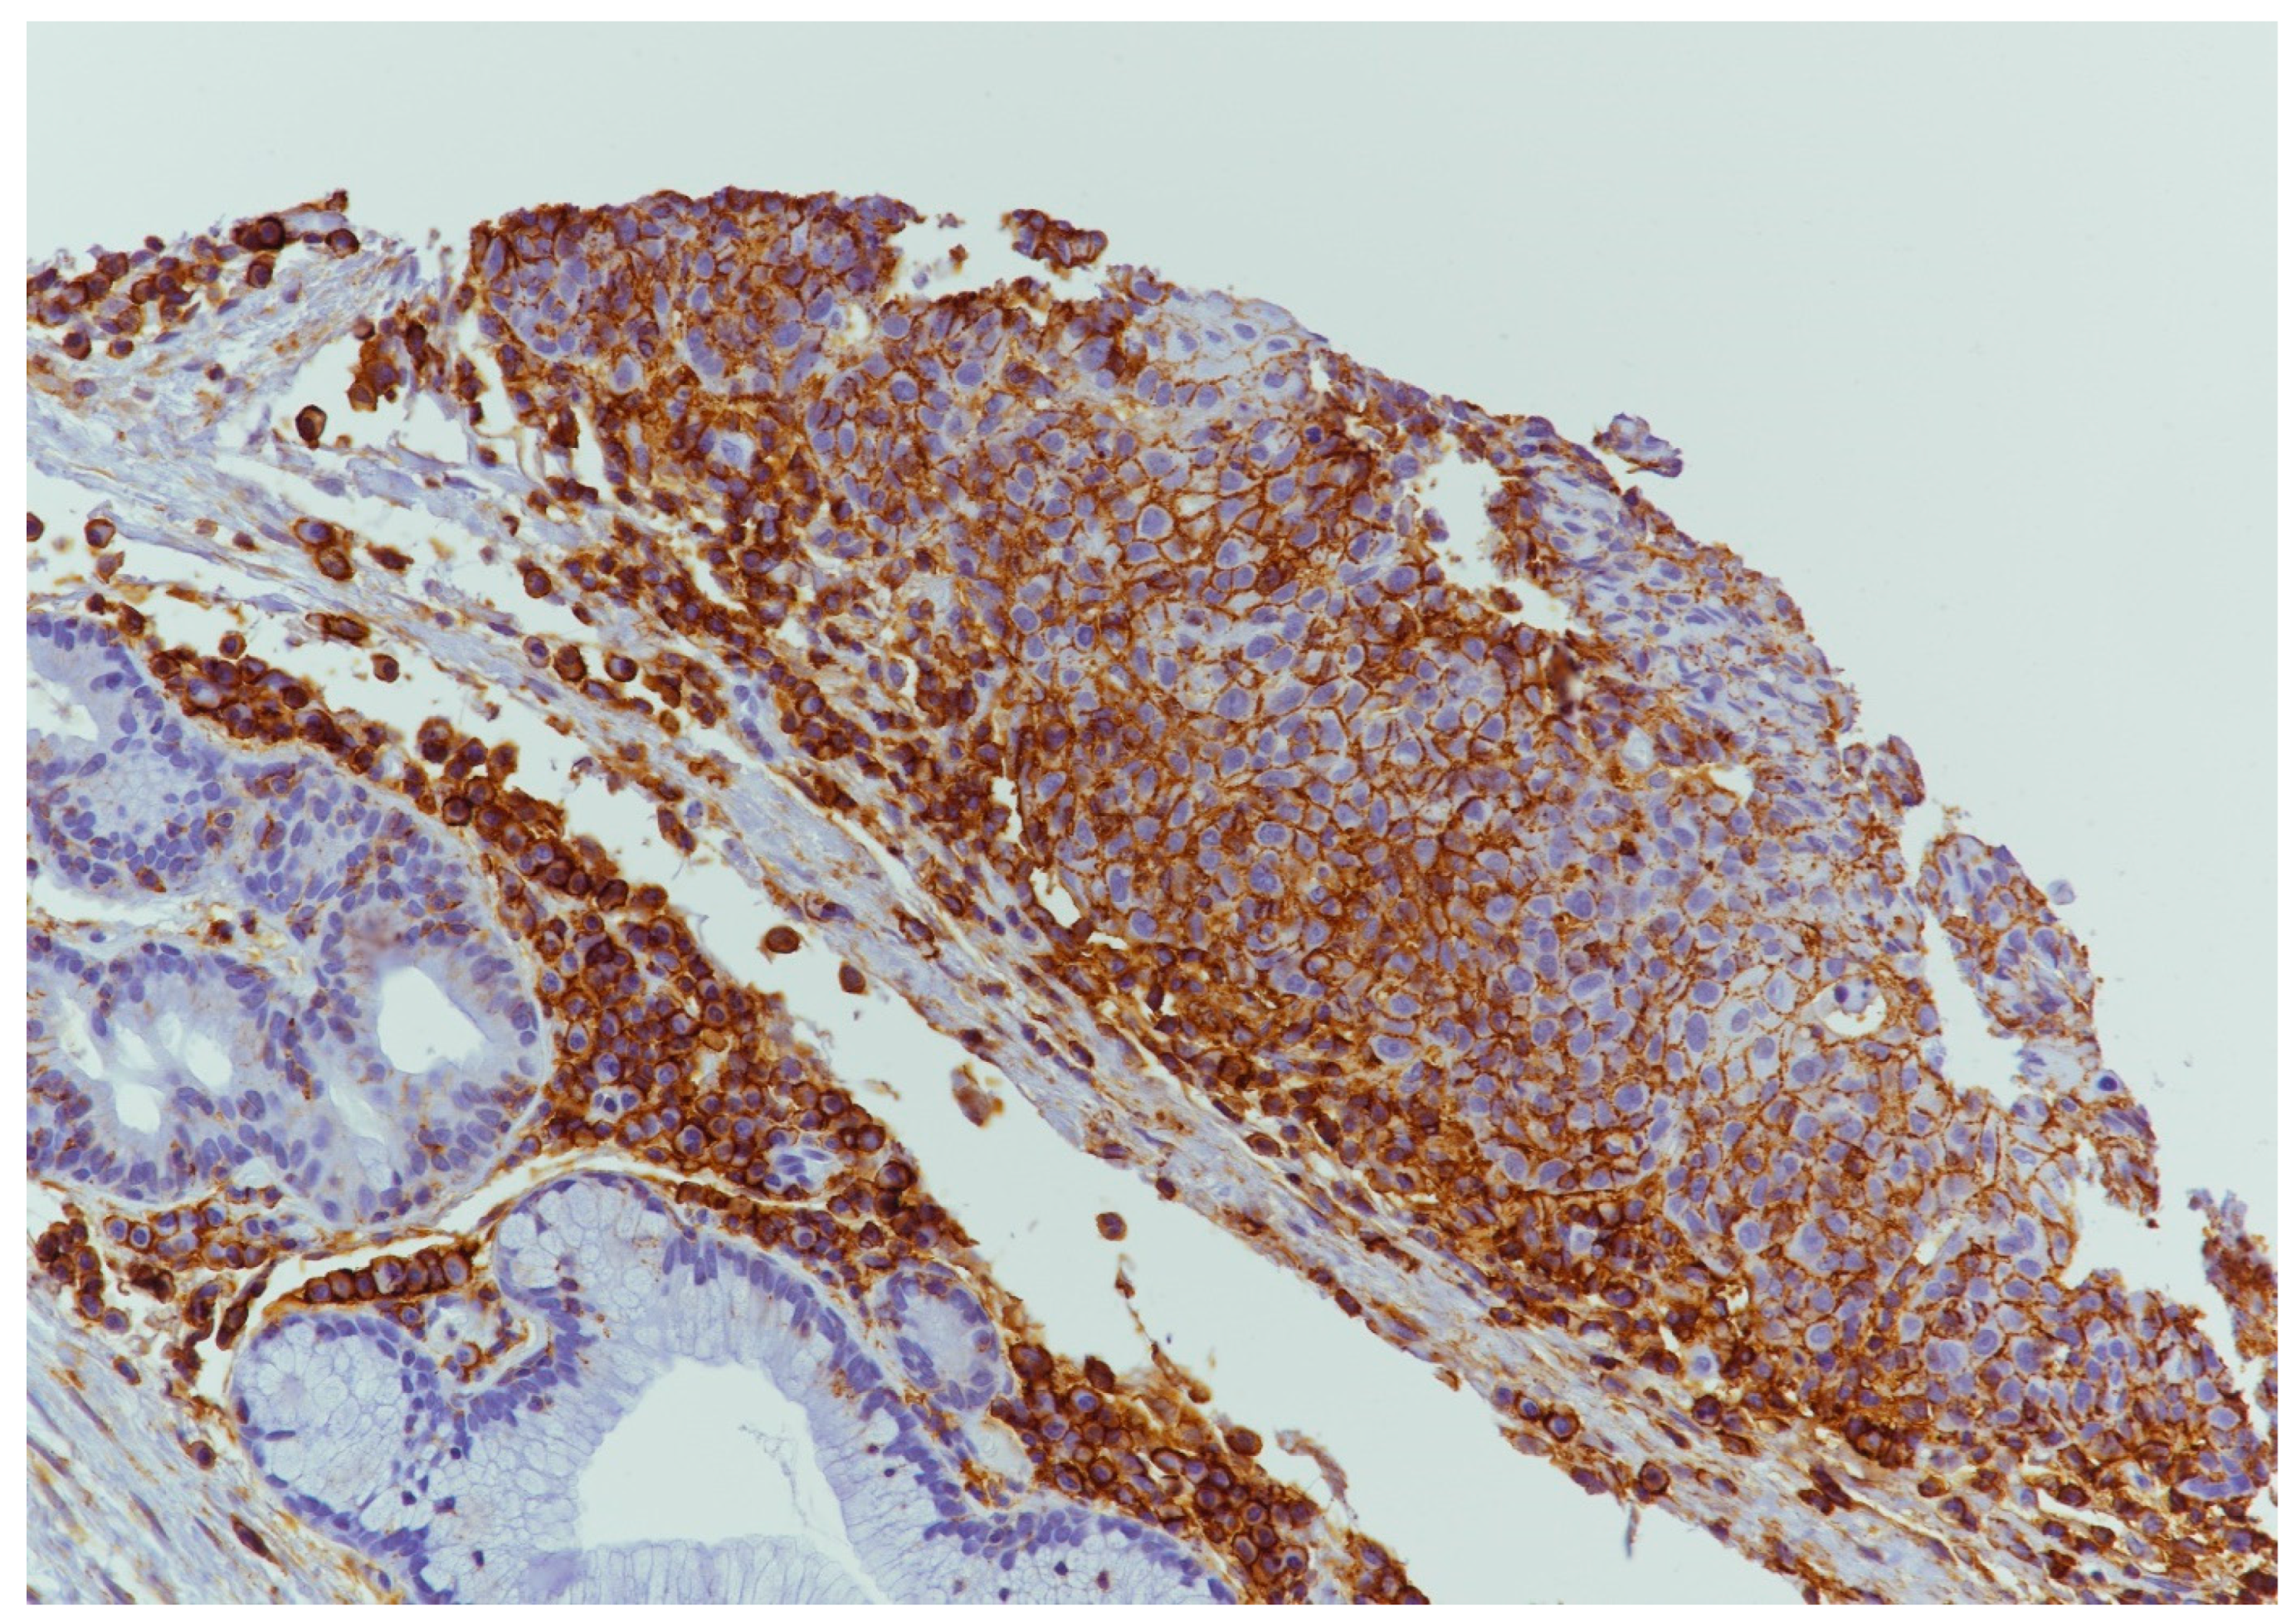

4.4. ATG7 Expression